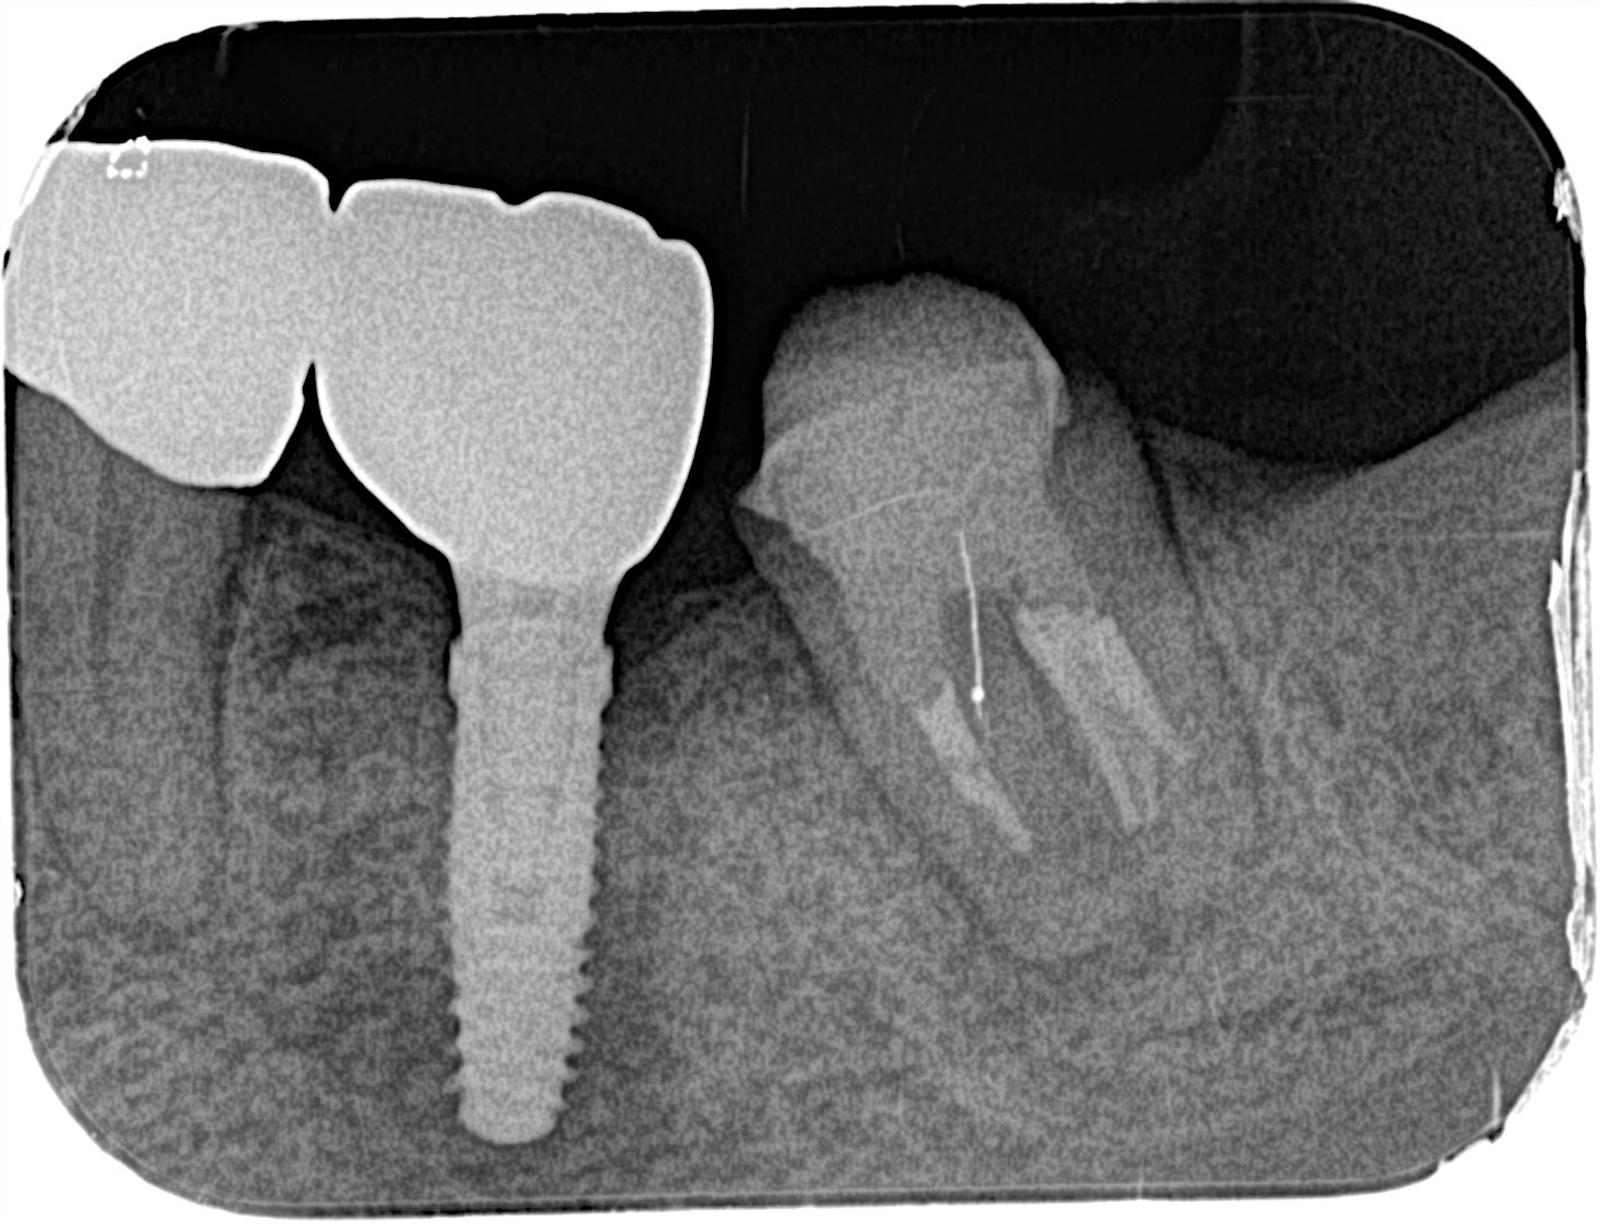

ブリッジを支える歯に過度な負荷がかかり、骨が吸収されたケース。

前医では抜歯と診断されたが、インプラントへの置き換えと根の治療により、歯を残すことができた。